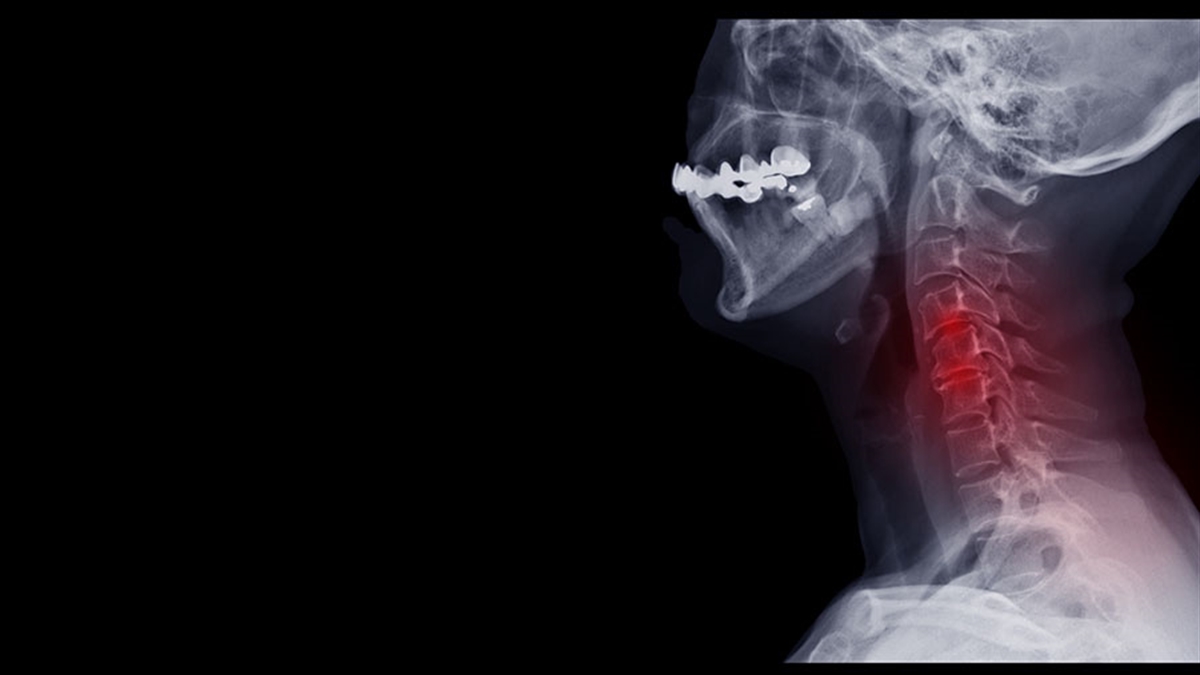

Baş Boyun Cerrahisi

Baş Boyun Kanserlerine Genel Bakış